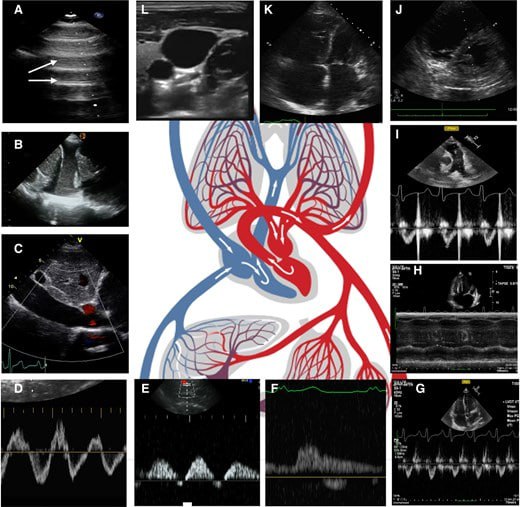

Острые состояния в кардиологии требуют немедленного принятия решений и быстрых, точных диагностических подходов. Ультразвуковое исследование сердца (УЗИ сердца) обеспечивает неинвазивную визуализацию структур и функций сердца в режиме реального времени, что способствует принятию быстрых и точных решений.

Подробно изложен патофизиологический подход к применению ультразвука (с указанием рекомендуемых для определения показателей) при таких состояниях как:

- кардиогенный и вазоплегический шок;

-острый инфаркт миокарда;

-острая декомпенсация сердечной недостаточности;

- острая тяжёлая клапанная регургитация;

-острая тромбоэмболия лёгочной артерии;

- тампонада сердца;

- спонтанный пневмоторакс;

- острая обструкция выходного тракта левого желудочка;

- перипартальная кардиомиопатия;

-острый миокардит;

- синдром Такоцубо;

-острые аортальные синдромы;

- остановка сердца.